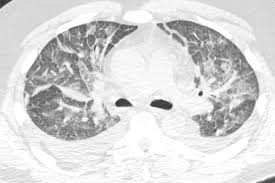

Definitions of acute lung injury (ali) and acute respiratory distress syndrome (ards) have varied over time. Ards, or acute respiratory distress syndrome, is a lung condition that leads to low oxygen levels in the blood. A survey of academic intensivists' use of neuromuscular blockade in subjects with ards. Use of dynamic ct in acute respiratory distress syndrome (ards) with comparison of positive and negative pressure ventilation. .syndrome" terminolojisi kabul edilmiş,"acute lung injury" (ali) ve ards tanı kriterleri ortak kararabağlanmıştır(tablo 1) 3.bu tarife göre ali, ards'nin erken safhası olarakgösterilmektedir.

Signs and symptoms of ards. Ards can be life threatening. Definitions of acute lung injury (ali) and acute respiratory distress syndrome (ards) have varied over time. Learn about ards or acute respiratory distress syndrome. Use of dynamic ct in acute respiratory distress syndrome (ards) with comparison of positive and negative pressure ventilation. The berlin definition of ards: National heart, lung, and blood institute acute respiratory distress syndrome (ards). Acute respiratory distress syndrome (ards).

Ards caused by pulmonary and extrapulmonary disease: Therapy of acute respiratory distress syndrome: Ards nursing lecture (acute respiratory distress syndrome) with free quiz to help nursing students prep for nclex. Ards happens when the lungs become severely inflamed from an infection or injury. Ards, or acute respiratory distress syndrome, is a lung condition that leads to low oxygen levels in the blood. Learn about ards or acute respiratory distress syndrome. Home lung disease & respiratory health center topic guide. .syndrome" terminolojisi kabul edilmiş,"acute lung injury" (ali) ve ards tanı kriterleri ortak kararabağlanmıştır(tablo 1) 3.bu tarife göre ali, ards'nin erken safhası olarakgösterilmektedir. Acute respiratory distress syndrome (ards) with other comorbidities that eventually leads to death. Acute respiratory distress syndrome (ards) is an acute, diffuse, inflammatory form of lung injury that is associated with a variety of etiologies. Use of dynamic ct in acute respiratory distress syndrome (ards) with comparison of positive and negative pressure ventilation. Survey of german ards centers and scientific l. The main complication in ards is that fluid leaks into the lungs making breathing difficult or.

Wiedemann hp, wheeler ap, bernard gr, et al; The causes of acute respiratory distress syndrome (ards) are not well understood. Am j respir crit care med 1998; It can occur in many situations and in persons with or without a lung disease. Ards happens when the lungs become severely inflamed from an infection or injury. Ards, or acute respiratory distress syndrome, is a lung condition that leads to low oxygen levels in the blood. Acute respiratory distress syndrome (ards) is a form of acute lung injury and occurs as a result of a severe pulmonary injury that causes alveolar damage heterogeneously throughout the lung. Neuromuscular blockers in early acute respiratory distress syndrome. Acute respiratory distress syndrome (ards) occurs when fluid builds up in the tiny, elastic air sacs (alveoli) in your lungs. Acute respiratory distress syndrome (ards). Ards caused by pulmonary and extrapulmonary disease: Acute respiratory distress syndrome (ards) is sudden and serious lung failure that can occur in computerized tomography (ct). Acute respiratory distress syndrome (ards) with other comorbidities that eventually leads to death.